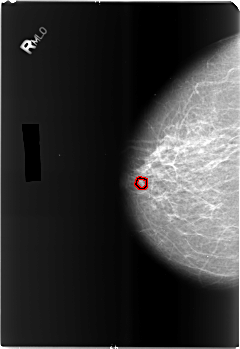

B_3489_1.RIGHT_CC

FILE: B_3489_1.RIGHT_CC.OVERLAY

TOTAL_ABNORMALITIES 1

ABNORMALITY 1

LESION_TYPE CALCIFICATION TYPE PLEOMORPHIC DISTRIBUTION CLUSTERED

ASSESSMENT 4

SUBTLETY 3

PATHOLOGY BENIGN

TOTAL_OUTLINES 1

BOUNDARY